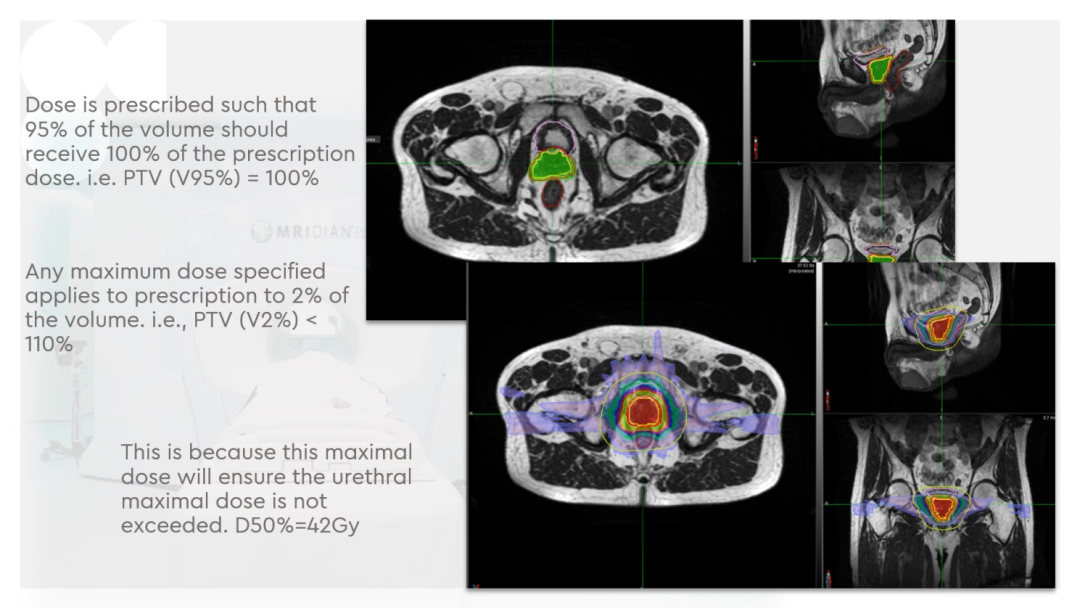

Dr. CamilleriÌåÏÖ£¬£¬£¬£¬£¬£¬ËûÃÇÔÚ×öÔÚÏß×Ô˳Ӧ·ÅÁƵÄʱ¼ä£¬£¬£¬£¬£¬£¬ÎªÁËÌá¸ßËÙÂÊ£¬£¬£¬£¬£¬£¬½ö¶Ô°ÐÇøÍâ·Å3cmÒÔÄÚµÄΣ¼°Æ÷¹ÙµÄת±ä¾ÙÐÐ×Ô˳Ӧµ÷½â»òÖØÐ¹´»ÂÖÀª£¬£¬£¬£¬£¬£¬¼ûFigure 13¡£¡£¡£¡£¡£¡£¡£ÕâÑù¿ÉÒÔËõ¶ÌÂÖÀª¹´»µÄʱ¼ä¡£¡£¡£¡£¡£¡£¡£¹ØÓÚ·ÅÁÆÍýÏ룬£¬£¬£¬£¬£¬Ê¹µÃ95%µÄ°ÐÇøÌå»ý½ÓÊܵ½100%µÄ´¦·½¼ÁÁ¿ÁýÕÖ£¬£¬£¬£¬£¬£¬²¢½«×î´ó¼ÁÁ¿ÏÞÖÆÎª2%µÄ°ÐÇøÌå»ý²»Áè¼Ý´¦·½¼ÁÁ¿µÄ110%£¬£¬£¬£¬£¬£¬ÕâÑù¾ÍÄܰü¹ÜÔÚͼÏñÉϺÜÄÑÏÔʾµÄÄòµÀ²»»á³¬Á¿£¬£¬£¬£¬£¬£¬¼ûFigure 14¡£¡£¡£¡£¡£¡£¡£ÁíÍ⣬£¬£¬£¬£¬£¬ÔÚÖÆ×÷·ÅÁÆÍýÏëʱ£¬£¬£¬£¬£¬£¬½«PTV·ÖΪPTV LOWºÍPTV High£¬£¬£¬£¬£¬£¬PTVºÍΣ¼°Æ÷¹ÙÖØµþµÄ²¿·ÖΪPTV LOW£¬£¬£¬£¬£¬£¬½«PTV LOWµÄ¼ÁÁ¿Ä¿µÄÉ趨ÔÚΣ¼°Æ÷¹ÙµÄÄÍÊܼÁÁ¿ÒÔÏ£¬£¬£¬£¬£¬£¬ÕâÑù¾ÍÄܰü¹ÜΣ¼°Æ÷¹Ù²»³¬Á¿£¬£¬£¬£¬£¬£¬¼ûFigure 15¡£¡£¡£¡£¡£¡£¡£